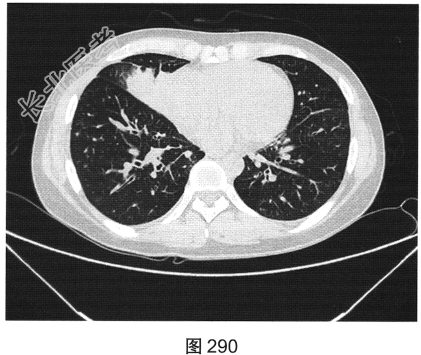

- [材料题] 患者女性,43岁,因“确诊肺低分化腺癌1周”就诊。患者于2014年11月无明显诱因出现咳嗽、咳痰,无胸闷胸痛,无咯血,无发热、乏力、体重减轻等。自服中药治疗,止咳效果尚可。2015年4月22日在山海关人民医院行胸部CT:显示①慢性支气管炎继发感染,建议结合临床及病史考虑;②右侧中间段支气管及中叶支气管壁增厚、管腔狭窄伴右肺中叶阻塞性肺不张,右侧肺门及纵隔多发淋巴结增大,建议增强扫描。后补做增强CT:右肺中叶支气管增厚,管腔狭窄伴阻塞性肺不张,考虑右侧中心型肺癌伴纵隔多发淋巴结增大,建议行支气管镜检查。支气管镜取活检病理:示低分化腺(右肺中叶)癌,建议做免疫组织化学检测,以进一步明确诊断。于北京肿瘤医院行PET/CT检查:①右肺中叶支气管起始部位高代谢结节,符合中心型肺癌表现;右肺中叶部位阻塞性不张,不张肺内高代谢结节,倾向肺内转移;双肺多发转移结节;双锁骨上区、左胸肌间、纵隔及双肺门多发淋巴结转移。②脑部未见明显高代谢征象,建议行增强MRI检查。③双叶甲状腺炎性或非特异性摄取,建议行B超及甲状腺功能检查。患者精神状态良好,体力、食欲、睡眠均正常,体重无明显变化,大便、排尿正常,为进一步检查及治疗,门诊以“肺癌”收入院。2015年5月5日在我院行CT检查,如图288~图295所示。